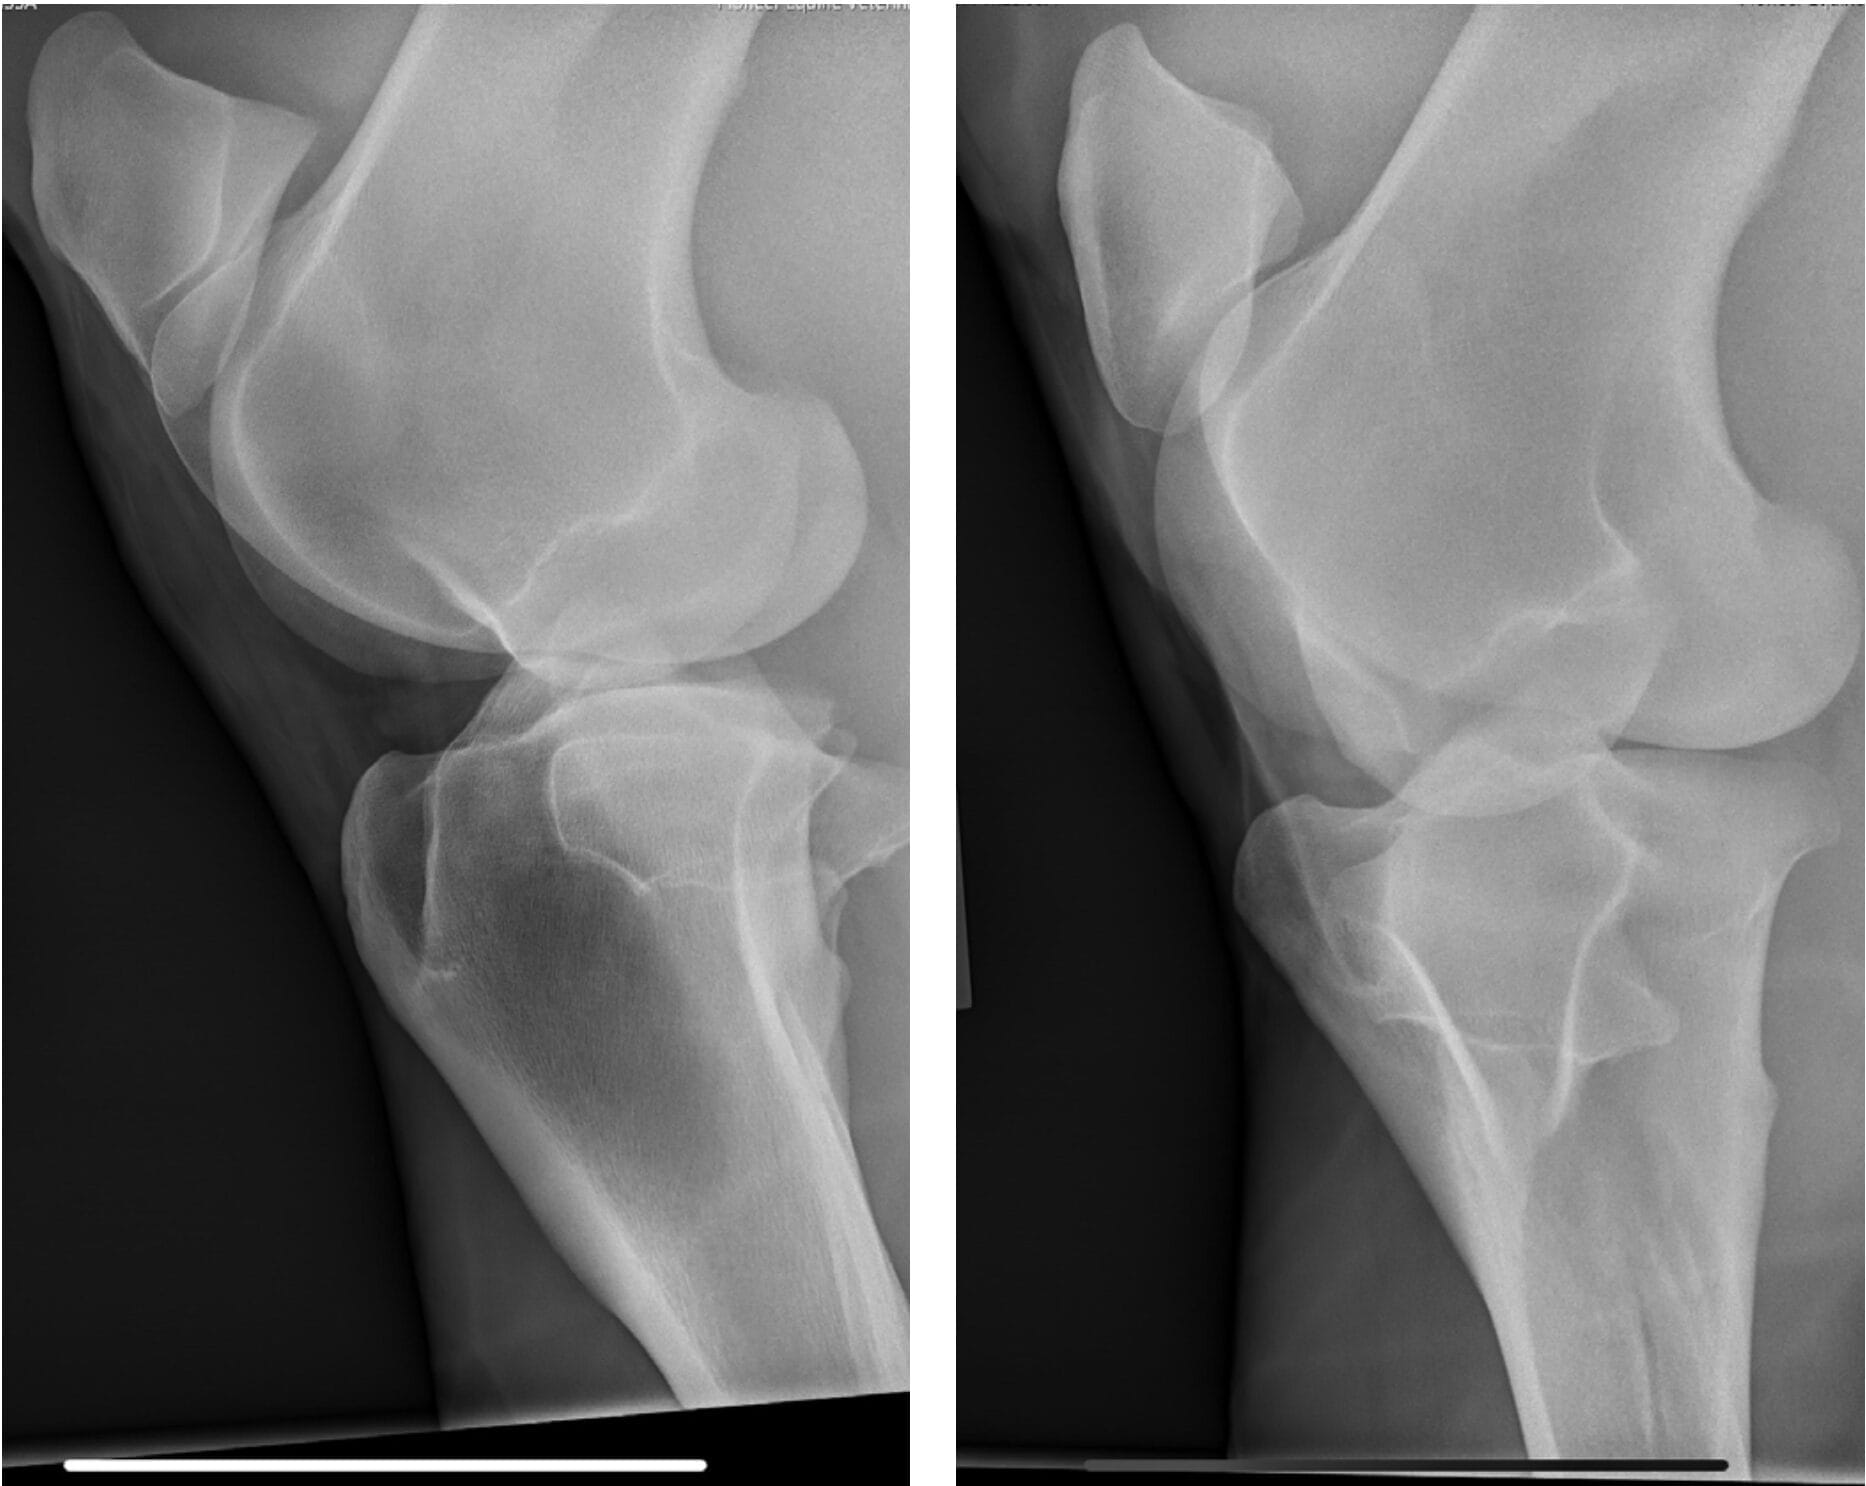

In April 2023, Bella developed a right hind lameness that was characterised by a toe drag, decreased push and mild abduction of the limb. The lameness was worse with the leg on the outside of the circle. She was negative to lower limb flexion and 1+ out of 5 positive to upper limb flexion. Lameness resolved with an intra-articular medial femorotibial block. Radiographs of the right stifle were unremarkable.